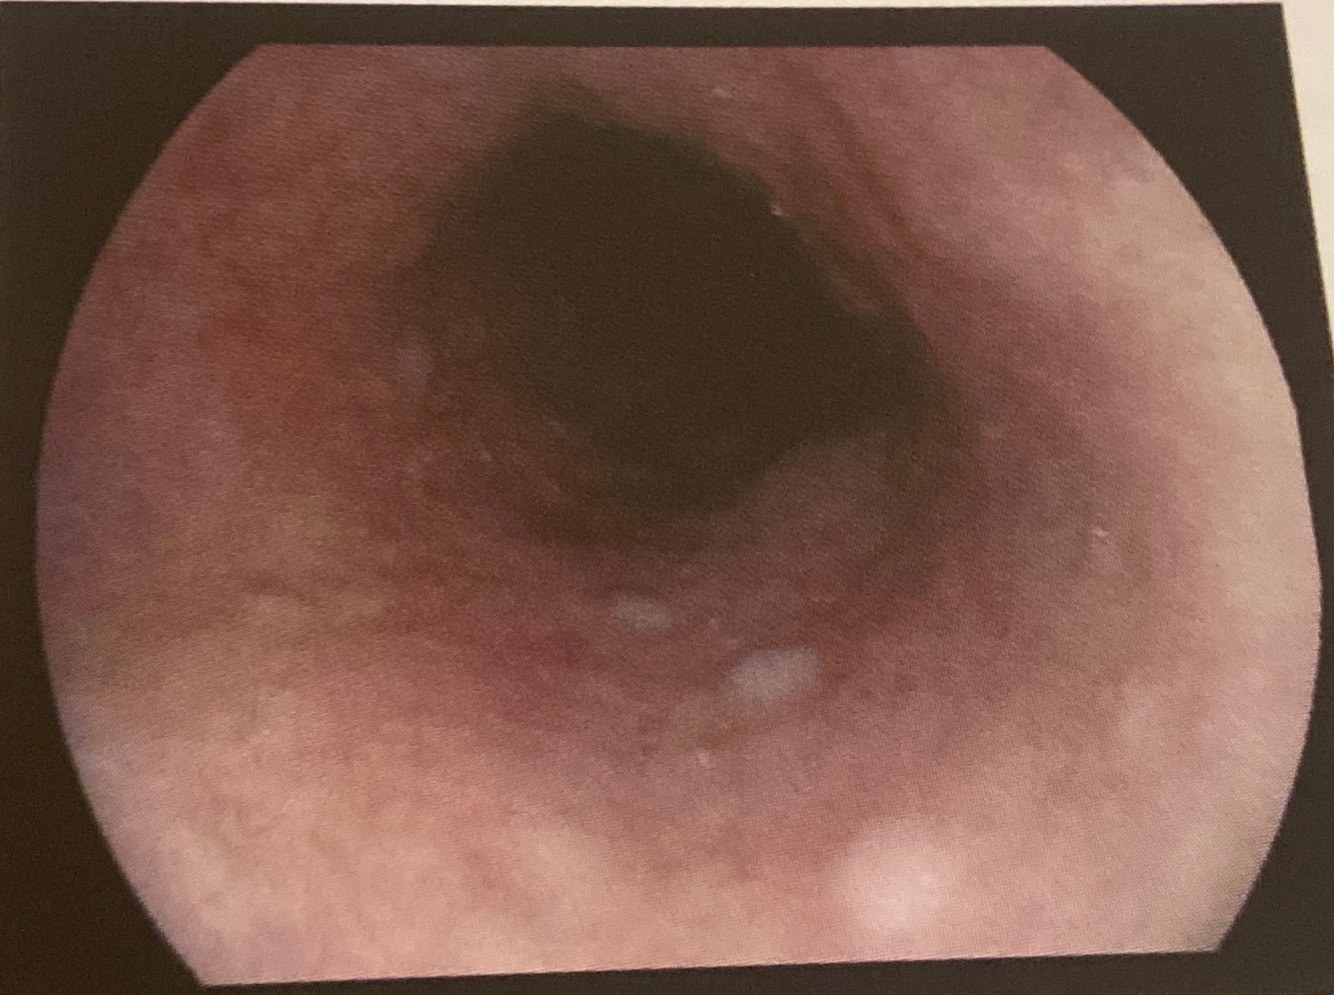

Esôfago

Espessamento difuso da mucosa, discretos sulcos longitudinais associados a tênue exsudato brancacento e predomínio de ondulações transversais finas Esofagite eosinofilica